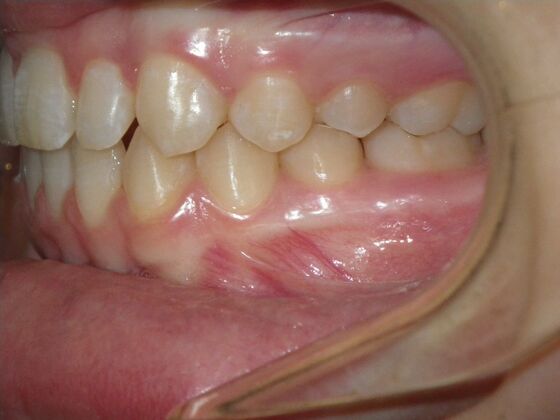

This case presents with a dental midline discrepancy. The upper incisors are tipped toward the palate, which prevents the lower incisors from establishing proper arch form. The upper right molar has drifted forward, causing the upper midline to be skewed to her left. By distalizing the upper left molar, we can correct the midline discrepancy. Lastly, both upper and lower arches need expansion. All of this was completed with conventional straight wire appliances within 2 years.